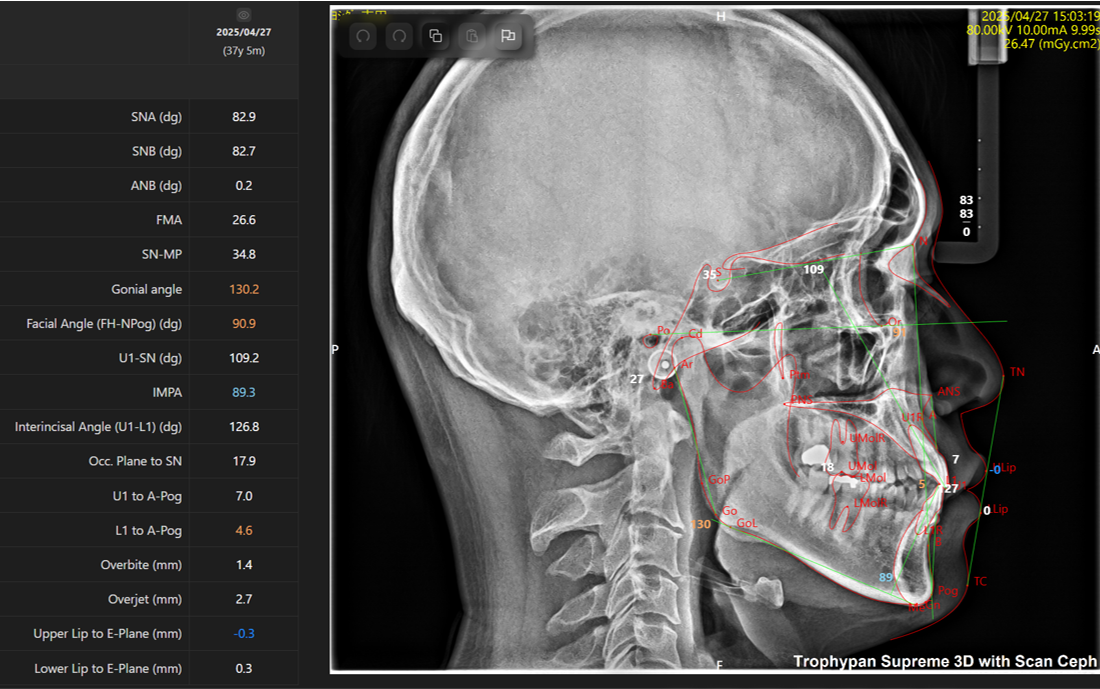

当院ではMoon Aligner Systemという診断ソフトを用いて、撮影後3~5分でレントゲン写真から以下の画像のようにAIが自動で分析値を即座に出してくれます。

この機能により、現時点の問題点や、治療方針について確信をもって説明することが可能になります。